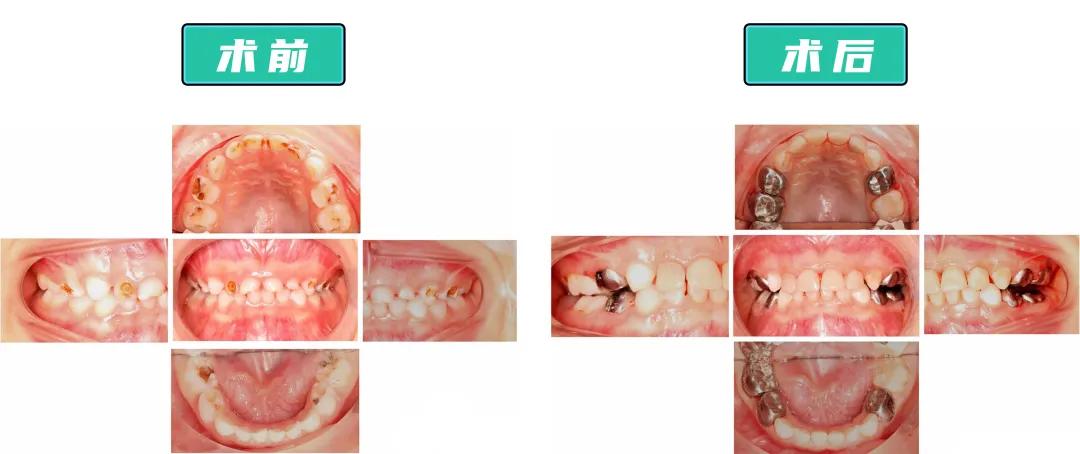

医生给童童没那么严重的前牙“套上”了透明树脂预成冠,针对要受力咀嚼、不太影响美观的后牙,“套上”了相对不易磨损脱落、可承受压力更大、性价比更高的金属预成冠。

整个过程治疗了17颗龋齿,做了12颗预成冠,一次性解决了童童的口腔问题。